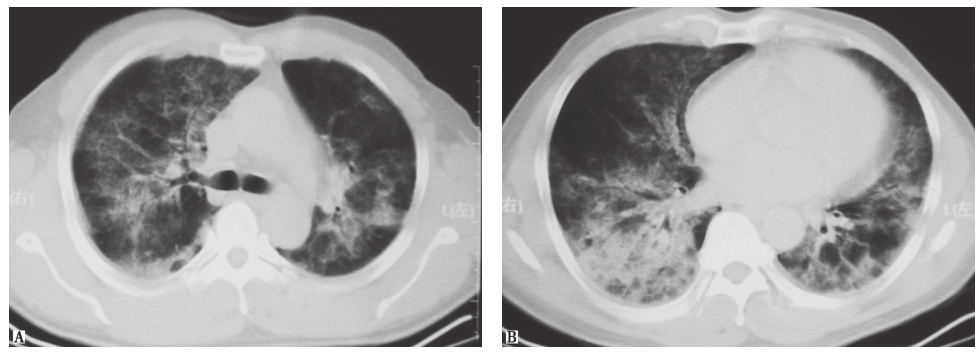

胸部CT:入院前3个月胸部CT示双肺弥漫性间质病变,可见磨玻璃和斑片高密度影,伴部分间质纤维化(图1)。予激素、抗感染及对症治疗后复查胸部CT,见双肺间质性病变较前增多。

图1胸部CT表现(2013-02-02)

发病初期,胸部CT见双肺间质弥漫性磨玻璃样渗出伴斑片高密度影,累及叶间裂